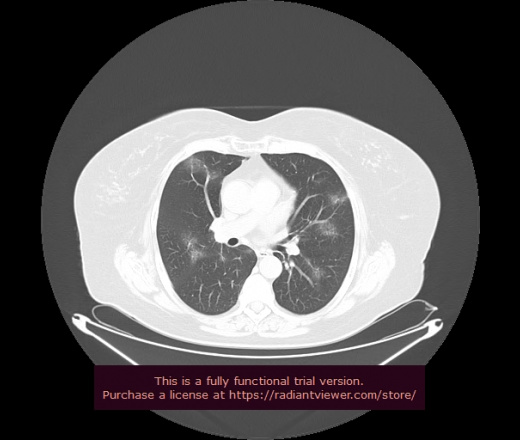

Уважаемые коллеги, если имеется интерес, сможете ли Вы спрогнозировать дальнейшее +-одинаковое течение процесса у 4 данных разных пациентов? Зацепиться где-то можно очень просто, где-то нельзя.